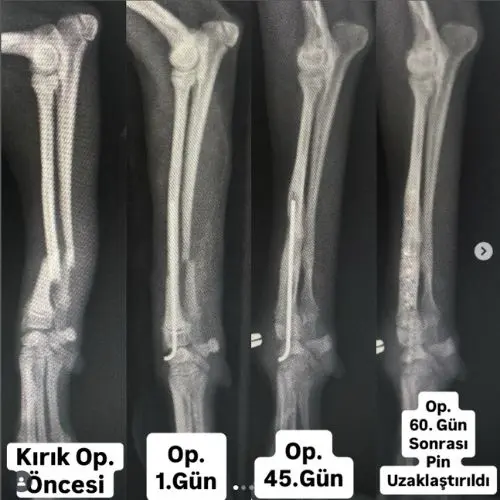

Pin ile Sabitleme ve Düzeltme: İnce metal çubuklar kullanılarak kırıklar ve eklem deformiteleri düzeltilir.

Plak ile Sabitleme ve Düzeltme: Kemiklerin doğru şekilde birleşmesi için cerrahi olarak plak ve vida sistemi uygulanır.